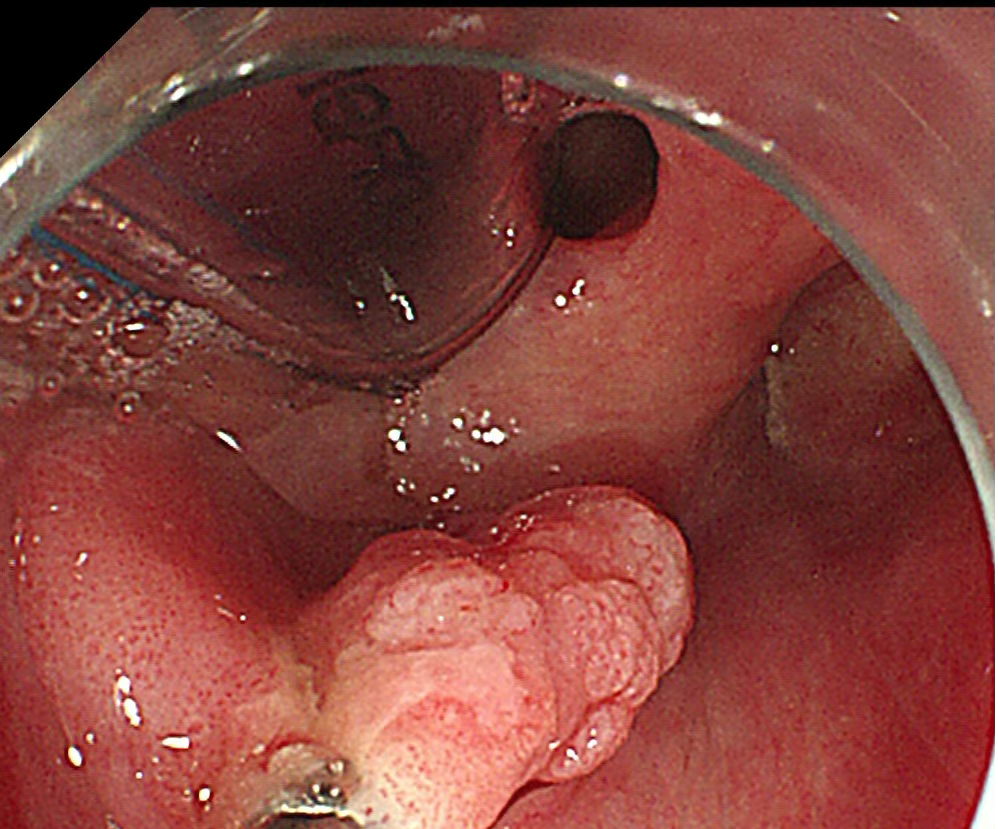

咽部病灶

1.(食管33处)食管糜烂型鳞状细胞癌,Ⅱ级,肿瘤大小0.6×0.3cm,癌组织局限于黏膜内(M2);淋巴管及血管内未见癌栓;送检组织四周及基底部切缘未见癌组织。免疫组化结果显示:CD34(未见癌栓),D2-40(未见癌栓),Desmin(平滑肌+),E-cadherin(+),Ki-67(index≈40%),P53(+,突变型)。

2.(下咽部)隆起型鳞状细胞癌,Ⅱ级,肿瘤大小1.8x1.2,癌组织侵及黏膜固有层;淋巴管及血管内未见癌栓;切缘及基底部切缘未见癌组织,(肿物距基底部切缘约200微米)。免疫组化结果显示:CD34(未见癌栓),C-erbB-2(1+),CK5/6(+),D2-40(未见癌栓),EGFR(+)、Ki-67(index≈50%),P53(-),P63(+)。